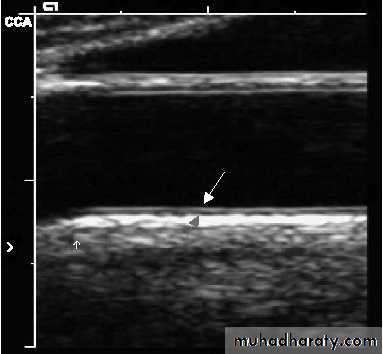

Magnetic Resonance Image (MRI) of a Stenotic Carotid Artery Bifurcation

left carotid artery bifurcation with an atherosclerotic plaque with a necrotic corerelatively normal artery

Chu B et al. Stroke 2004;8:2444–2448.

Computed Tomography (CT)Showing Atherosclerotic Artery

B-mode UltrasoundReproduced with permission from Kastelein, JJP et al. Am Heart J 2005;149:234–239.